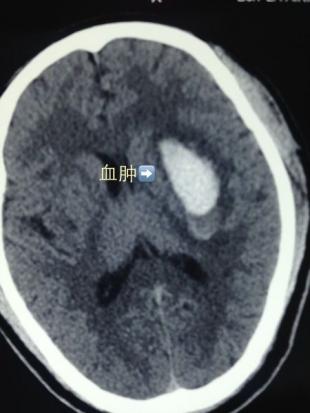

不行,夹闭过渡,有一支动脉不显影了,快速调整夹闭位置……”日前,国际著名脑血管介入专家、二炮总医院副院长姜卫剑率团队为一名战士成功